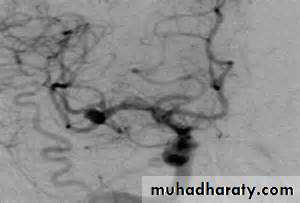

extravasations of blood into the subarachnoid space between the pial and arachnoid membranes80% are due to a ruptured berry aneurysm

Rupture of arteriovenous malformations (AVMs) accounting for 10% of cases of SAHIncreased blood pressure

Vessels imaging

10-20% of patients with clinically diagnosed SAH (on CT and/or lumbar puncture) have negative angiographic findings. A repeat angiogram is usually required in 10-21 days in such cases.MD-CTA derives from its noninvasiveness and a sensitivity and specificity comparable to that of cerebral angiography. This technique is beneficial in very unstable patients who cannot undergo angiography or in emergent settings prior to operative intervention for clot evacuation